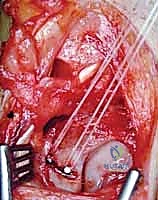

Intraoperative Surgical Step